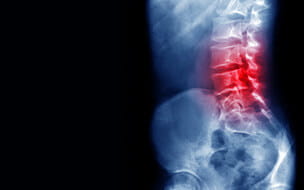

Sciatica - Causes, Diagnosis and Treatment Options

Back Pain - Causes, Non-Surgical & Surgical Treatment Options

When Back Pain Is Not Just Back Pain - Sciatica and Degenerative Lumbar Spinal Stenosis